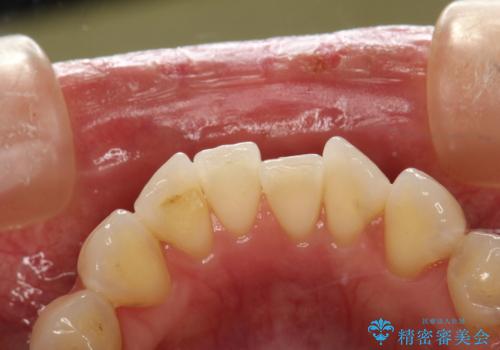

PMTC30分コース(保険外治療)を行いました。かなり久しぶりの歯科医院へ来院とのことで、プラーク(歯垢)・歯石・ステイン(着色)が付着していました。汚れを除去し、本来のご自身の歯質にすることでなにか異常があった際に発見しやすくなります。

PMTCで汚れを除去することは、虫歯や歯周病・口臭予防に効果的です。

また、今回はクリーニング後に、何か所か虫歯や治療途中のままの部分が発見されました。今後は定期的なメンテナンス・クリーニングと併用しながら虫歯の治療を行っていく予定です。